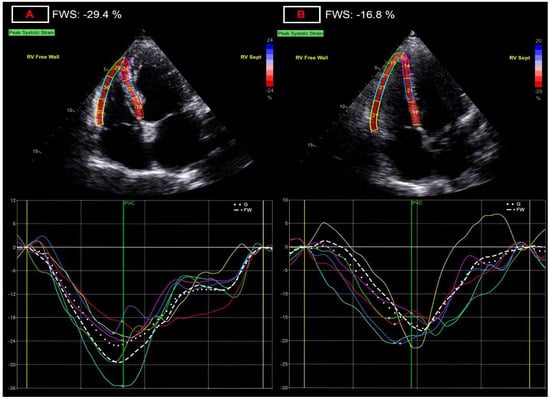

Among parameters representing contractile function of the LV, global longitudinal strain showed one of the most significant differences between the two groups [−20.3 (−21.1–−19.0) vs. −19.1 (−20.4–−17.6)%; p = 0.0007], with a relative decrease of 5.9% (Figure 1). The decreased GLS values correlated with many parameters of LV dimension and function in univariate correlation analysis (Table 5) but correlated only with LV stroke volume index (partial correlation coefficient, rpartial: −0.284; p = 0.029), and the left atrial volume index (rpartial: −0.343; p = 0.008) in the multivariate regression analysis.

Figure 1. Representation of alterations of global longitudinal strain (GLS) measurement. (A) panel: normal left ventricular global longitudinal strain of −22.7%; (B) panel: decreased left ventricular global longitudinal strain of −16.2%, after COVID-19 infection.